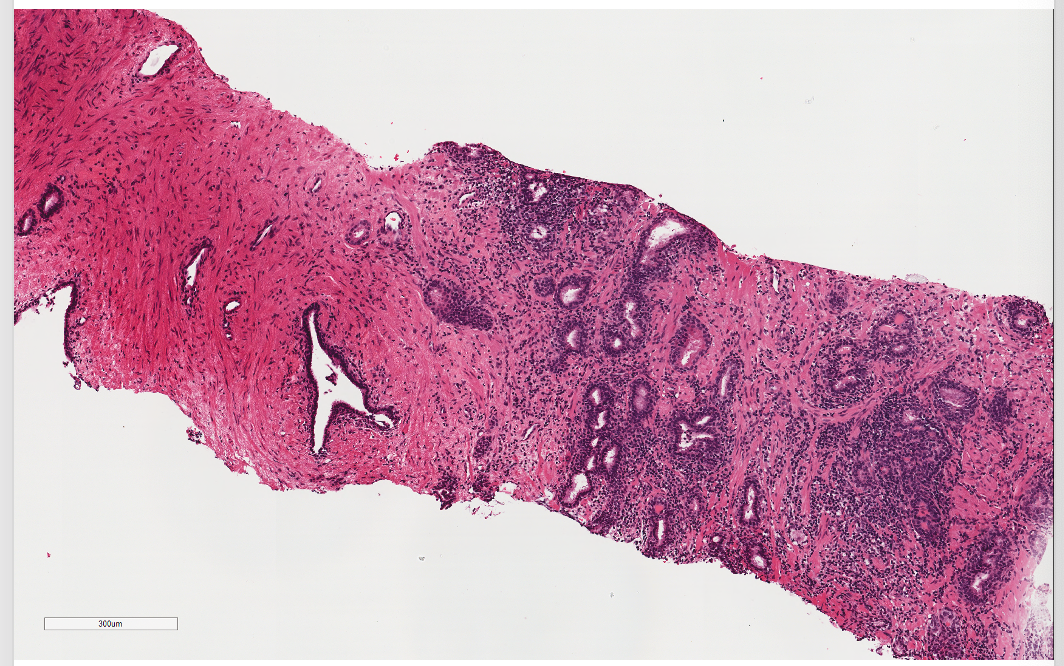

What is shown here?

Blue cells agreggatred

Get a lot of infiltration of inflammatory cells

Chronic inflammation is shown here

What is prostatitis?

Inflammatory conditions of the prostate

Common